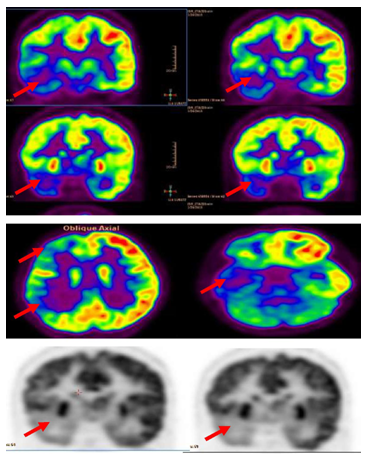

A twelve years old right handed boy a school student referred to the epilepsy monitoring unit for epilepsy surgery evaluation of pharmaco-resistant epilepsy that failed several antiepileptic drugs monotherapy and poly therapy trials. The patient is a product of full term normal spontaneous vaginal delivery with normal mile stones. He had febrile convulsions at the age of one year with no recurrence and had family history of epilepsy with one sibling and one paternal cousin had epilepsy with generalized tonic clonic seizures in remission on anti epileptic drugs. The first generalized tonic clonic seizure occurred at the age of seven years preceded by an aura of rising abdominal pain and followed by post ictal fatigue. Generalized tonic clonic seizures recurred at weekly interval with and without the preceding abdominal pain. At times the abdominal pain occurs with no generalized tonic clonic seizures but followed by lack of concentration and fatigue. The seizures occurred mainly during wakefulness but could occur during sleep. The patient never achieved seizure remission and never developed status epilepticus despite frequent seizures. He was admitted to the epilepsy monitoring unit EMU at the age of twelve years. He was on two antiepileptic drugs namely topiramate one hundred milligram twice daily and lamotrigine two hundred milligram twice daily with almost weekly seizures. His neurological, general and systemic examinations were normal. The patient was kept on his antiepileptic drugs and had five days video electroencephalography EEG monitoring using ten-twenty system scalp EEG electrodes with additional anterior temporal electrodes T1 electrode on the left anterior temporal region and T2 electrode on the right anterior temporal region respectively. During the video EEG monitoring the patient developed four stereotyped electroclinical seizures. Three were during wakefulness and one during sleep. No generalized tonic clonic seizures recorded. The seizures were preceded by abdominal pain in one seizure only. The seizure semiology starts with abrupt asymmetric abduction of both upper and lower limbs with prominent tonic and dystonic contraction of the left upper and lower limbs and adversive eyes and head deviation to the left with proximal automatic movements of the right arm and leg. The duration of seizure was fifty to sixty seconds during which the patient was unresponsive with early recovery of comprehension and speech in the post ictal phase. The ictal EEG onset starts with right frontal regional suppression followed by slow activity of the right hemisphere in all recorded seizures. The interictal EEG showed asymmetric background with excessive slow transients of three to five hertz activity in the right hemisphere with frequent repetitive interictal spikes and polyspike-wave discharges at right frontopolar region intermixed with two to three slow transients (Figure 1). The electroclinical seizures recorded favored right hemispheric epilepsy with early engagement of the right frontal regions. Preadmission MRI of the brain showed right hippocampal sclerosis HS. Ictal single-photon emission computed tomography SPECT with technetium-99m hexamethyl-propylene amine oxime Tc-99m HMPAO injected at twenty five seconds after ictal EEG onset of the fourth seizure showed right medial and lateral temporal lobe hyperpefusion (Figure 2). Interictal positron emission tomography with F-18 fluorodeoxyglucose F-18 FDG-PET showed right hemisphere hypometabolism with marked reduction of F-18-FDG metabolism at right frontal, right temporal, right parietal and right thalamic regions (Figure 3). As the initial MRI diagnosis of right HS could not alone explain the seizures of the patient with a high probability of additional right hemispheric neocortical focus a follow up high resolution three Tesla MRI brain was performed prior to invasive EEG recording. The MRI brain clearly demonstrated right temporal pole cortical dysplasia in addition to the right HS (Figure 4).The diagnosis of dual pathology was made with right temporal pole cortical dysplasia and right HS the so called HS+. The patient underwent directly epilepsy surgery without invasive EEG implantation .He received extensive right temporal lobectomy under intraoperative electrocorticography and regions with active spiking were removed (Figure 5). Histopathology of the resected right hippocampus showed HS and tissue from the right temporal pole confirmed the presence of focal cortical dysplasia type III. The patient had no post surgical complications. The patient became seizure free and six month post epilepsy surgery interictal EEG was normal. Currently the patient is seizure free with significant cognitive improvement at five years post epilepsy surgery on lamotrigine 25mg once daily .He attends high school and plans to be a teacher.

Figure 3 Interictal F-18 FDG-PET showed right hemisphere hypometabolism with marked reduction of F-18-FDG metabolism at right frontal , right temporal , right parietal and to less degree right thalamic regions (red arrows).